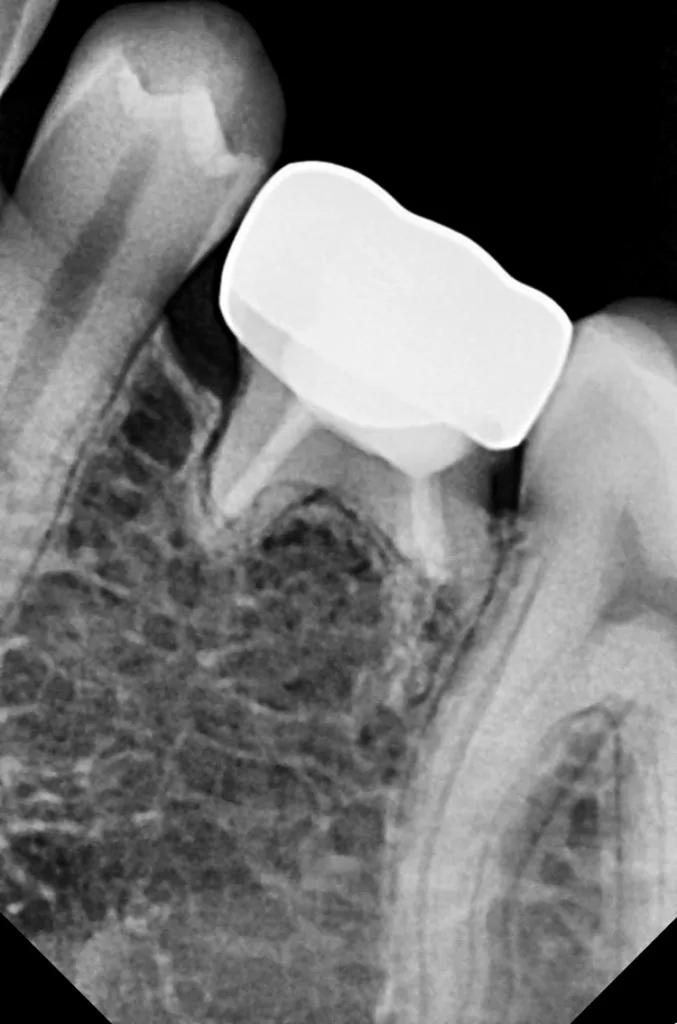

Die Länge wurde mittels Apexlocator (Propex Pixi, Dentsply Sirona, USA) ermittelt und mithilfe der Guttaperchastifte verifiziert. Nach einer finalen Spülung mit 5,25%igem NaOCl (5 ml für 2 Min.), gefolgt von 17%igem EDTA (3 ml für 1 Min.) und Kochsalzlösung (5 ml für 2 Min.), wurden die Wurzelkanäle getrocknet (Abb. 3) und mit einem hydraulischen Kalziumsilikatzement (MTA+, Cerkamed, Polen) obturiert (Abb. 2 und 4). Die finale Füllung erfolgte in derselben Sitzung mit einem fließfähigem Komposit (SDR flow+, Dentsply Sirona, USA) und Estelite ASTERIA OCE und A1B (Tokuyama, Japan) nach adhäsiver Vorbehandlung mit Optibond FL (Kerr, USA) (Abb. 5).

Nach 2,5 Jahren stellte sich der inzwischen 11,5 Jahre alte Patient erneut zu einer Nachkontrolle vor. Das Röntgenbild zeigte keine pathologischen Befunde und keine Anzeichen einer Wurzelresorption (Abb. 6). Ebenso lagen weder klinische Beschwerden noch Probleme mit der Okklusion vor.